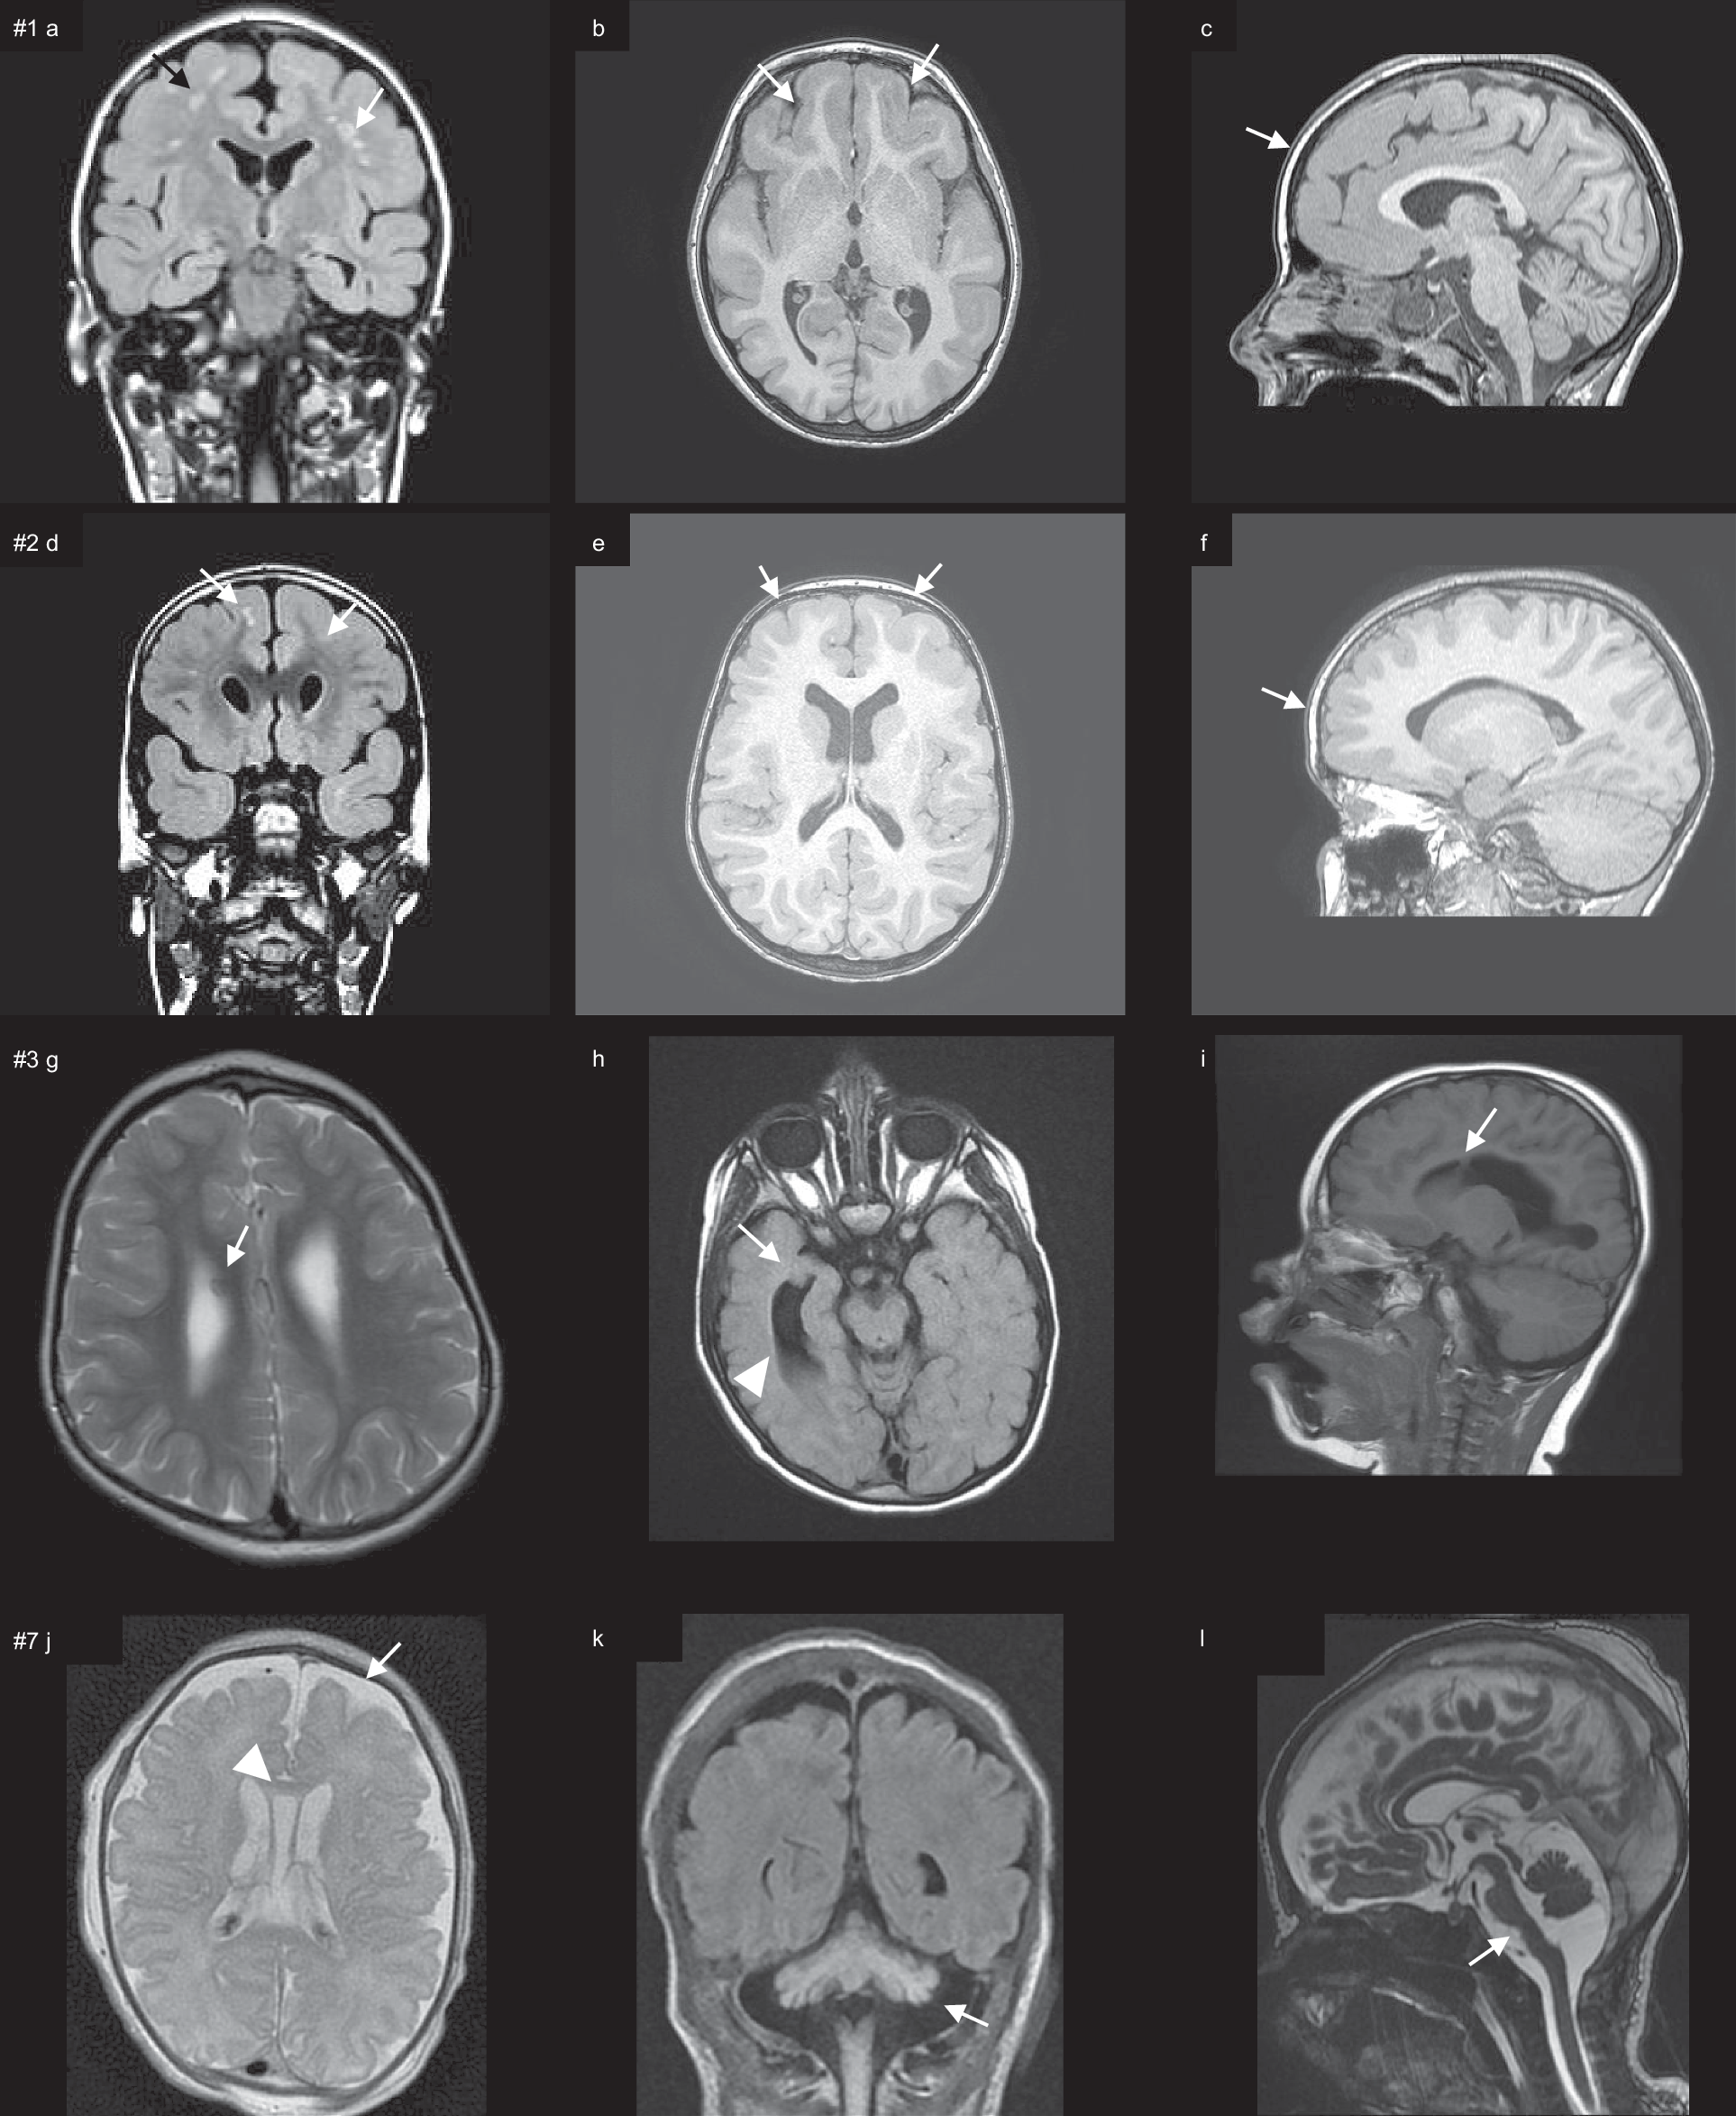

Fig. 2: Brain MRI of the patients.

a–c Coronal FLAIR, axial, and sagittal T1-weighted (T1W) brain MRI of patient #1 showing rounded subcortical white matter abnormalities, mainly in the frontal lobe, partly confluent (a, arrows) and pachygyria, with an antero-posterior gradient (b, c, arrows), sparing the occipital lobes. d–f Coronal FLAIR, axial, and sagittal T1W brain MRI of patient #2 showing isolated subcortical white matter abnormalities, mainly in the frontal lobe (d, arrows) and pachygyria, with an antero-posterior gradient, sparing the occipital lobes (e, f, arrows). g–i Axial T2W, axial T2W FLAIR, and sagittal T1W brain MRI of patient #3 showing microcephaly with normal gyration, focal gray matter heterotopia in the mesial wall (g), temporal horn (h), and frontal horn (i) of the right lateral ventricle and enlarged lateral ventricles (arrowhead). j–l Axial T2 weighted, coronal FLAIR and sagittal FIESTA brain MRI of patient #7 at 10 days of life showing septum pellucidum cyst (arrowhead) and mild enlargement of frontal subarachnoidal space (white arrow) (j), cerebral atrophy and cerebellar (k, arrow) and brainstem atrophy (l, arrow). Additional MR figures of patient #3 are available as Supplementary Fig. 2. Source data are provided in the Source Data File.